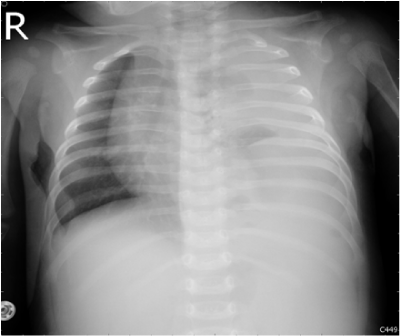

A 3-month-old male infant brought to our hospital with a one-day history of poor appetite and activity. Gestational history was uneventful with birth weight 3520grams and normal Apgar scores. He was healthy and had good weight gain before admission. The physical examination revealed severe respiratory distress, tachycardia, and acute ill looking. He had grunting, nasal flaring, and subcostal retraction. Air entry was reduced on the left side of the chest. His abdomen was flat with hypoactive bowel sounds. Chest radiograph showed opacification of left hemithorax with a moderate shift of mediastinum to right (Figure 1). He was admitted to the pediatric intensive care unit.

Figure 1 Initial chest x-ray showed left-sided opacification and a moderate shift of the mediastinum to the right.